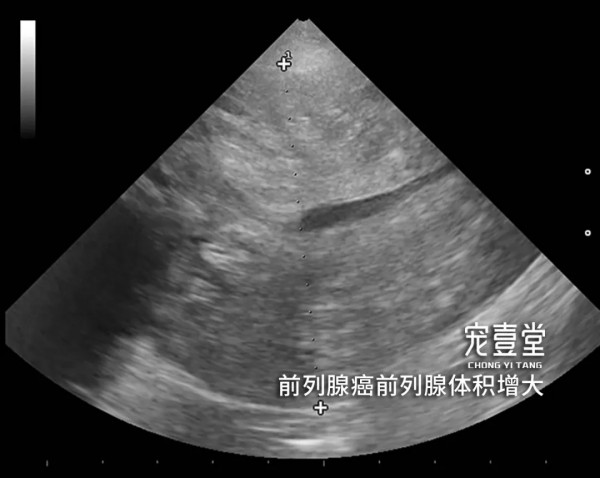

04【诊断标准】 1.根据临床症状、病史和体格检查做出初步诊断。触诊后腹部有明显疼痛反应,可摸到腹部肿块。 2.X线片可清晰看的见腹部前列腺位置的肿块。 3.超声检查可见前列腺明显增大并有强回声。当犬出现泌尿系统疾病时,除需检查肾脏、膀胱、前列腺外,睾丸及附睾也非常重要。前列腺的肿瘤有可能波及到或来自于睾丸及附睾的病变。 4.细针穿刺或活组织检查,可见肿瘤细胞。